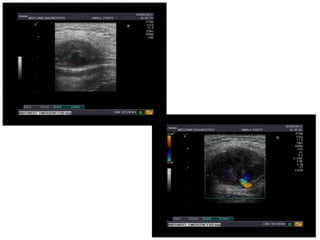

Axillary artery pseudoaneurysm

- 1.

USG GUIDED GRADEDCOMPRESSION

FOR

AXILLARY ARTERY PSUEDOANEURYSM

DR HEMANT DESHMUKH

DR AMOL BHALEKAR